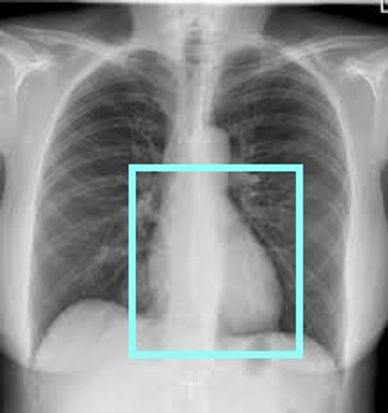

FOR ACQUISITION OF THE CCTA ENSURE THE SMALLEST FOV POSSIBLE TO ENSURE THE BEST SPACIAL RESOLUTION. SCAN SHOULD EXTEDND FROM THE CARINA THROUGH THE APEX OF THE HEART (SHOWN BELOW)

IMPORTANT DETAIL: IF THE PAITENT HAS A HISTORY OF CARDIAC STENTS/CABG SCAN SHOULD START FROM THE THORACIC INLET THROUGHT THE APEX OF THE HEART. MAKE SURE TO DOCUMENT THIS IN YOUR TECH NOTES.